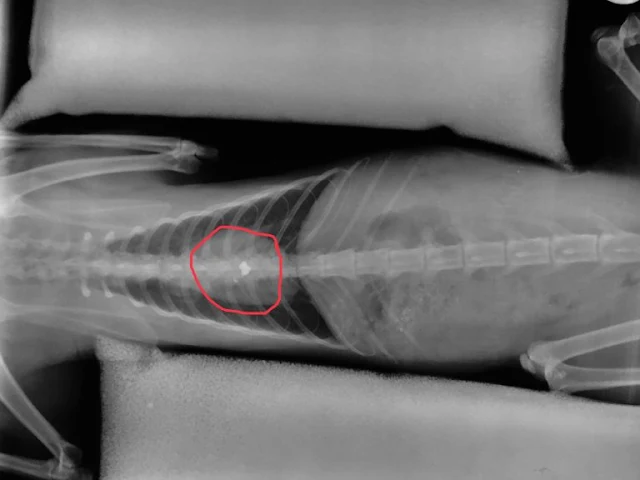

Σε 16 μήνες φυλάκιση καταδικάστηκε σήμερα 12 Ιουλίου 2019 εκπαιδευτικός, διευθυντής σε Λύκειο της Δευτεροβάθμιας Εκπαίδευσης του Δήμου Λαμιέων, ο οποίος εν ψυχρώ πυροβόλησε και άφησε παράλυτο από την μέση και κάτω έναν αδέσποτο γάτο. Το άτυχο ζώο πυροβολήθηκε από τον δράστη με αεροβόλο όπλο την ώρα που ζευγάρωνε.